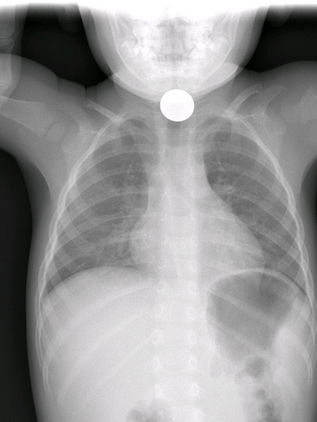

Hace unos días, un hecho puso a Chiapas de nueva cuenta en el foco nacional e internacional, para nada positivo: una menor de tan solo 13 años dio a luz y estuvo a punto de perder la vida, poniendo en evidencia que la entidad se mantiene en el primer lugar nacional en embarazos de niñas y adolescentes, según las Estadísticas de Nacimientos Registrados (ENR) 2024, publicadas por el INEGI, hace unas horas, la menor fue dada de alta, aunque su bebé se mantiene luchando por su vi